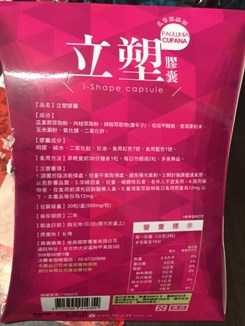

Supercut塑魔纖立塑膠囊的成分有:瓜拿那萃取粉、肉桂萃取粉、辣椒萃取物(唐辛子)、吡啶甲酸鉻、番瀉葉粉末、玉米澱粉、氧化鎂、二氧化矽。

之前上過相關課程,成分表是依照每項成分的多寡來排列順序,排在最前面的就是產品的主要成分!

食用方式:早晚餐前30分鐘各1粒,每日不超過2粒。(多食無益)

番瀉葉萃取物每日食用限量為12mg以下,

番瀉葉萃取物每日食用限量為12mg以下,